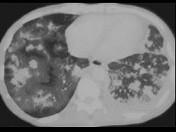

问题 女,26岁,全身不适,发热,咳嗽,咯血,有吸毒史,结合CT图像,最可能的诊断是 ( )

选项 A.卡波济肉瘤 B.肺癌 C.肺转移癌 D.肺结节病 E.肺结核

答案 A